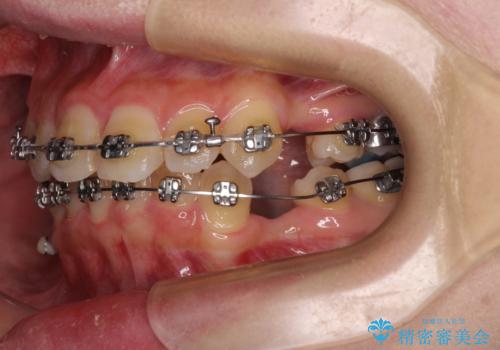

- 矯正装置

- メタルブラケット

- 3年1ヶ月

- 30回以上

- 上下の八重歯を気にして来院された患者様です。

非抜歯矯正で歯列を整えると、治療後に口元が今よりも突出する可能性が高かったため、上下左右の小臼歯4本を抜歯し、ワイヤー装置にて矯正治療を行うこととしました。

右上の八重歯の影響で、右側は上顎歯列が前方位の咬み合わせとなってしまっていたため、上顎は第一小臼歯を、下顎は第二小臼歯を抜歯することで咬み合わせや上下正中を調整することとしました。

第二小臼歯抜歯の治療となったため、やや時間はかかりましたが、概ね予想通りの期間で治療を終えることができました。